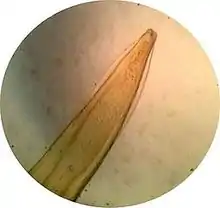

Morphologie

L'adulte mesure de 10 à 18 cm de longueur pour 1 à 2 mm de diamètre et présente une couleur blanc nacré. Il est souvent observé partiellement enroulé sur lui-même. L'extrémité antérieure portes deux ailes cervicales latérales dites en fer de lance. La bouche est entourée de trois lèvres développées.